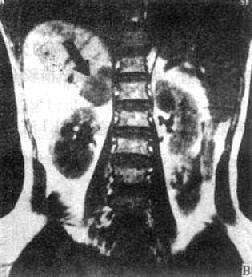

多囊肾平扫可见两肾增大,呈分叶状外形,内有多个囊肿,大小不等,壁薄。肾实质内可见钙化。还可发现肝、胰、脾的囊肿。平扫多可确诊。

MRI单纯囊肿呈长T1和长T2。边缘较清晰,内在信号均匀一致。多囊肾的囊肿可为单纯囊肿也可为出血性囊肿,故T1WI呈低信号或混杂信号,T2WI呈高信号或混杂信号,既可以均匀也可以不均匀。